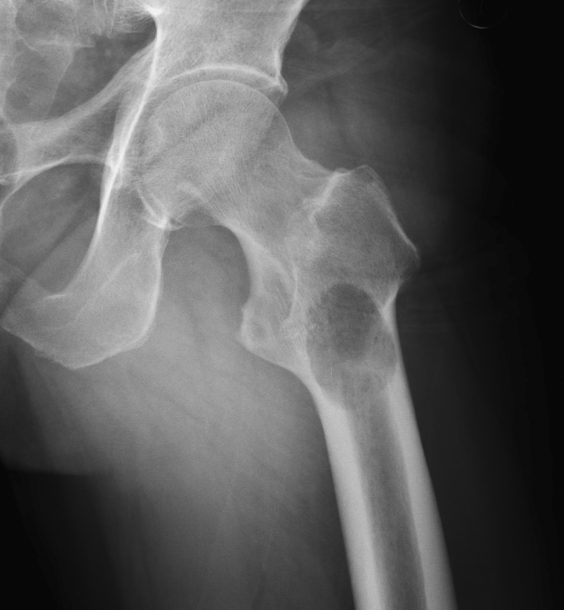

▌膨胀性破坏

膨胀性破坏是地图样破坏的特殊形式,影像学表现为骨质破坏区骨膨胀,周围可见不同程度扩张的骨壳(图 5、图 6、图 7、图 8)。膨胀性破坏是由于肿瘤从骨皮质内面破坏,骨外膜增生形成新生骨造成膨胀的。引起膨胀性破坏见于大多数良性肿瘤和肿瘤样病变如单纯性骨囊肿,动脉瘤样骨囊肿、内生软骨瘤和软骨粘液纤维瘤等,少数也可见于恶性肿瘤如转移瘤、骨髓瘤等。

图 8.膨胀性破坏:软骨粘液样纤维瘤